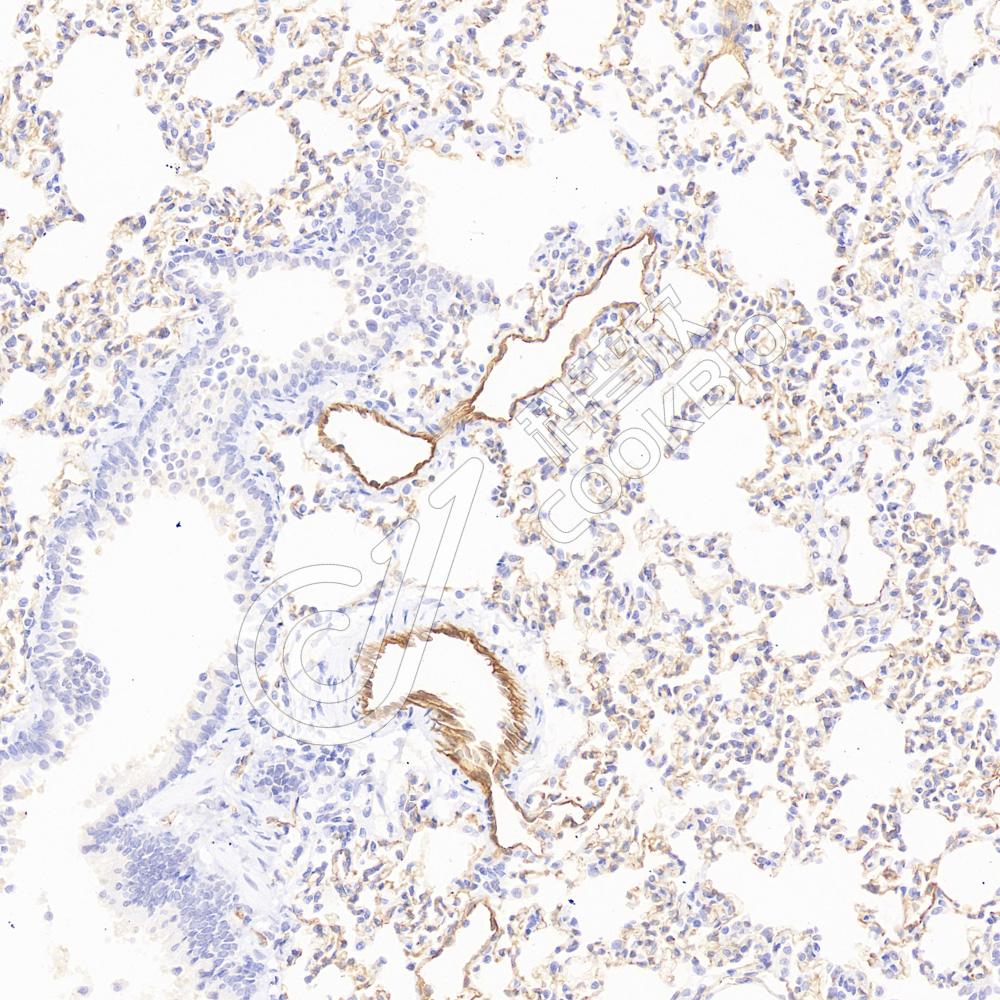

IHC检测CD31蛋白(货号 K236189).

样品: 小鼠肺, 4%多聚甲醛 (货号KSG1101) 固定12-24小时.

抗原修复: 柠檬酸抗原修复液(干粉, pH 6.0) (KSG1201), 高压锅均匀喷气计时2分钟.

—抗: 1: 600稀释, 4℃ 孵育过夜.

二抗: S-vision免疫组化多聚二抗(山羊抗小鼠), 即用型(货号KB3903), 室温孵育20分钟.

样品: 大鼠肺, 4%多聚甲醛 (货号KSG1101) 固定12-24小时.